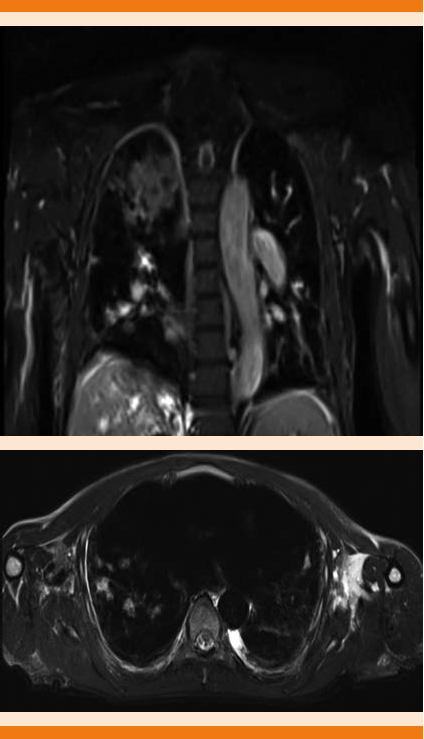

Malformación arteriovenosa pulmonar en la región apical derecha evidenciada en resonancia magnética nuclear de 69.4 x 26.1 x 51.4 mm (Figuras 2 y 3).

Figura 2 Imagen potenciada en T2, corte axial y sagital, en donde se observa una lesión irregular, heterogénea, predominantemente hiperintensa, en la región apical derecha, derrame pleural bilateral, existe, además, crecimiento global de las cavidades cardiacas, valorable en los cortes sagitales.

Figura 3 Imagen potenciada en T2, FAT SAT, corte coronal y axial, en donde se identifican en el hemitórax derecho múltiples lesiones irregulares, hiperintensas en relación con el resto del parénquima pulmonar, que demostraron corresponder a malformaciones arteriovenosas.